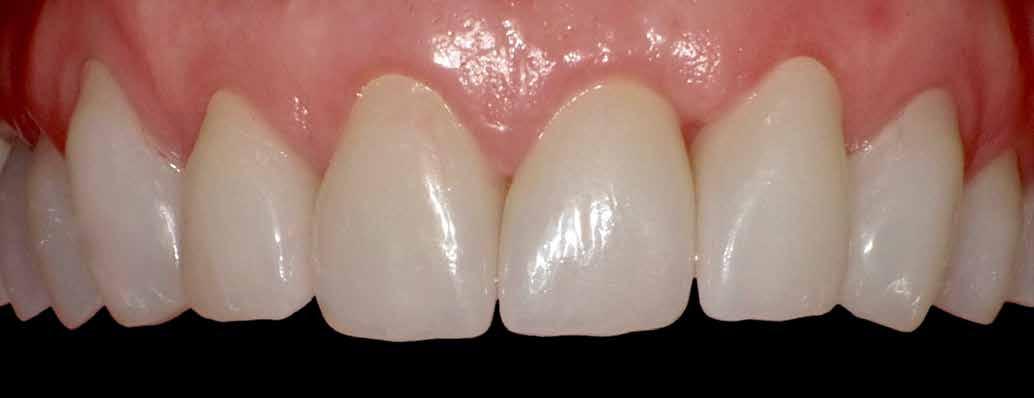

A végső restaurátumokat (héjakat és koronákat) Ce-

ramill Mind tervező program segítségével (AmannGirrbach) digitálisan megtervezték, majd frézgép segítségével (CeramillMotion 2, AmannGirrbach) li thium-diszilikát tömbökből (VITABLOCS TriLuxe forte for CeramillMotion 2, AmannGirrbach) kifaragták (10. ábra). Miután a fogpróba során ellenőrizték és megfelelőnek találták a pótlások széli záródásának a pontosságát, valamint az elkészült restaurátumok esztétikai megjelenését, ezután egy ajak- és szájterpesz került felhelyezésre (OptraGate, IvoclarVivadent).

A koronákat (1.3-1.1 és 2.1-2.3) és a héjakat (1.7-1.4, 2.4–2.7, 3.7-3.1, 4.1–4.7) fényrekötő adhezív rendszerrel rögzítették a pillérfogakhoz (Futurabond U ésBifix QM, VOCO). A polimerizációhoz egy nagy teljesítményű LED polimerizációs lámpát használtak (Celalux 3, VOCO), (1112. ábrák).

A kifolyó ragasztóanyagot ezt követően eltávolították, majd az okklúziót a T-Scantechnológia (Tekscan) segítségével ellenőrizték, majd a szükséges mértékben korrigálták. A véglegesen rögzített kerámiapótlás védelme érdekében a páciensnek a továbbiakban egy kivehető, átlátszó műanyag fogvédő sínt kellett viselnie. A pótlásokat 6 hónap múlva ellenőrizték. Az át adott fogpótlások stabilan rögzültek, és nem találtunk sérülésekre, repedésekre utaló jeleket (13-15. ábrák). A páciens arról is beszámolt, hogy a harapás megemelése óta megszűntek az őt rendszeresen gyötrő fejfájásai.